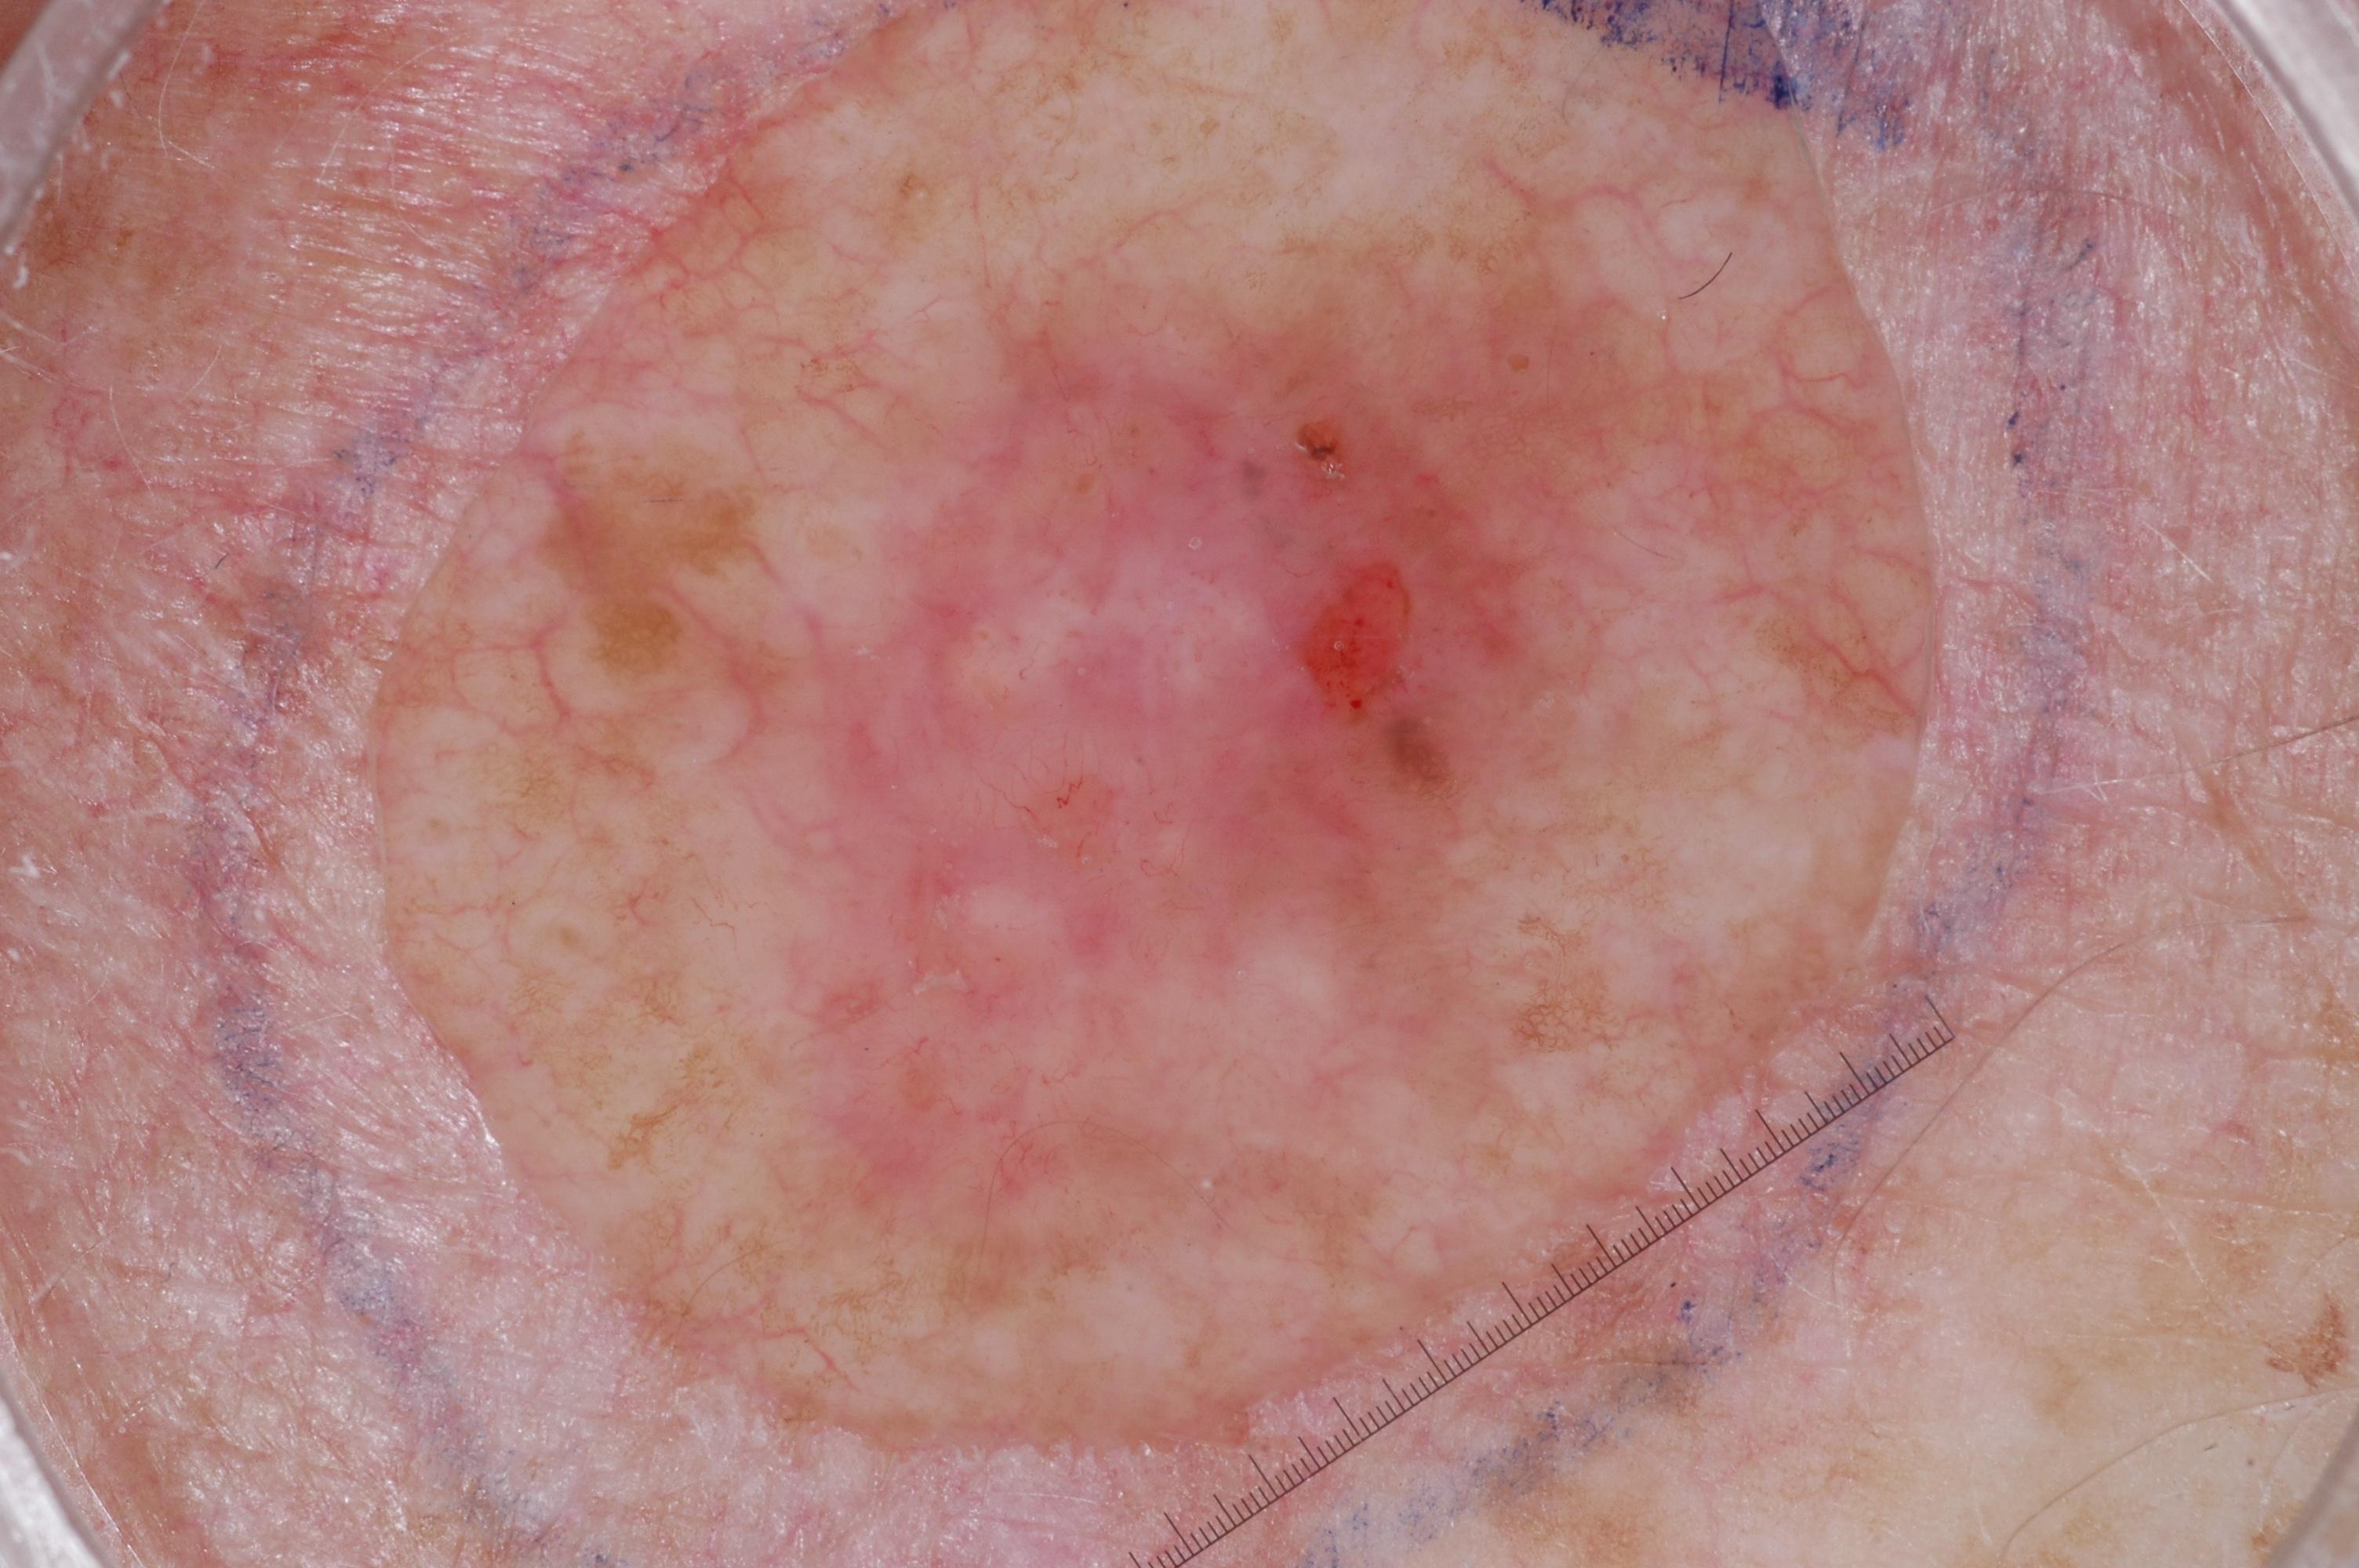

{

"age_approx": 60,

"anatom_site_general": "lower extremity",

"concomitant_biopsy": true,

"dermoscopic_type": "contact non-polarized",

"diagnosis_1": "Indeterminate",

"diagnosis_2": "Indeterminate melanocytic proliferations",

"diagnosis_3": "Atypical intraepithelial melanocytic proliferation",

"diagnosis_confirm_type": "histopathology",

"image_type": "dermoscopic",

"lesion_id": "IL_6551915",

"melanocytic": true,

"sex": "female"